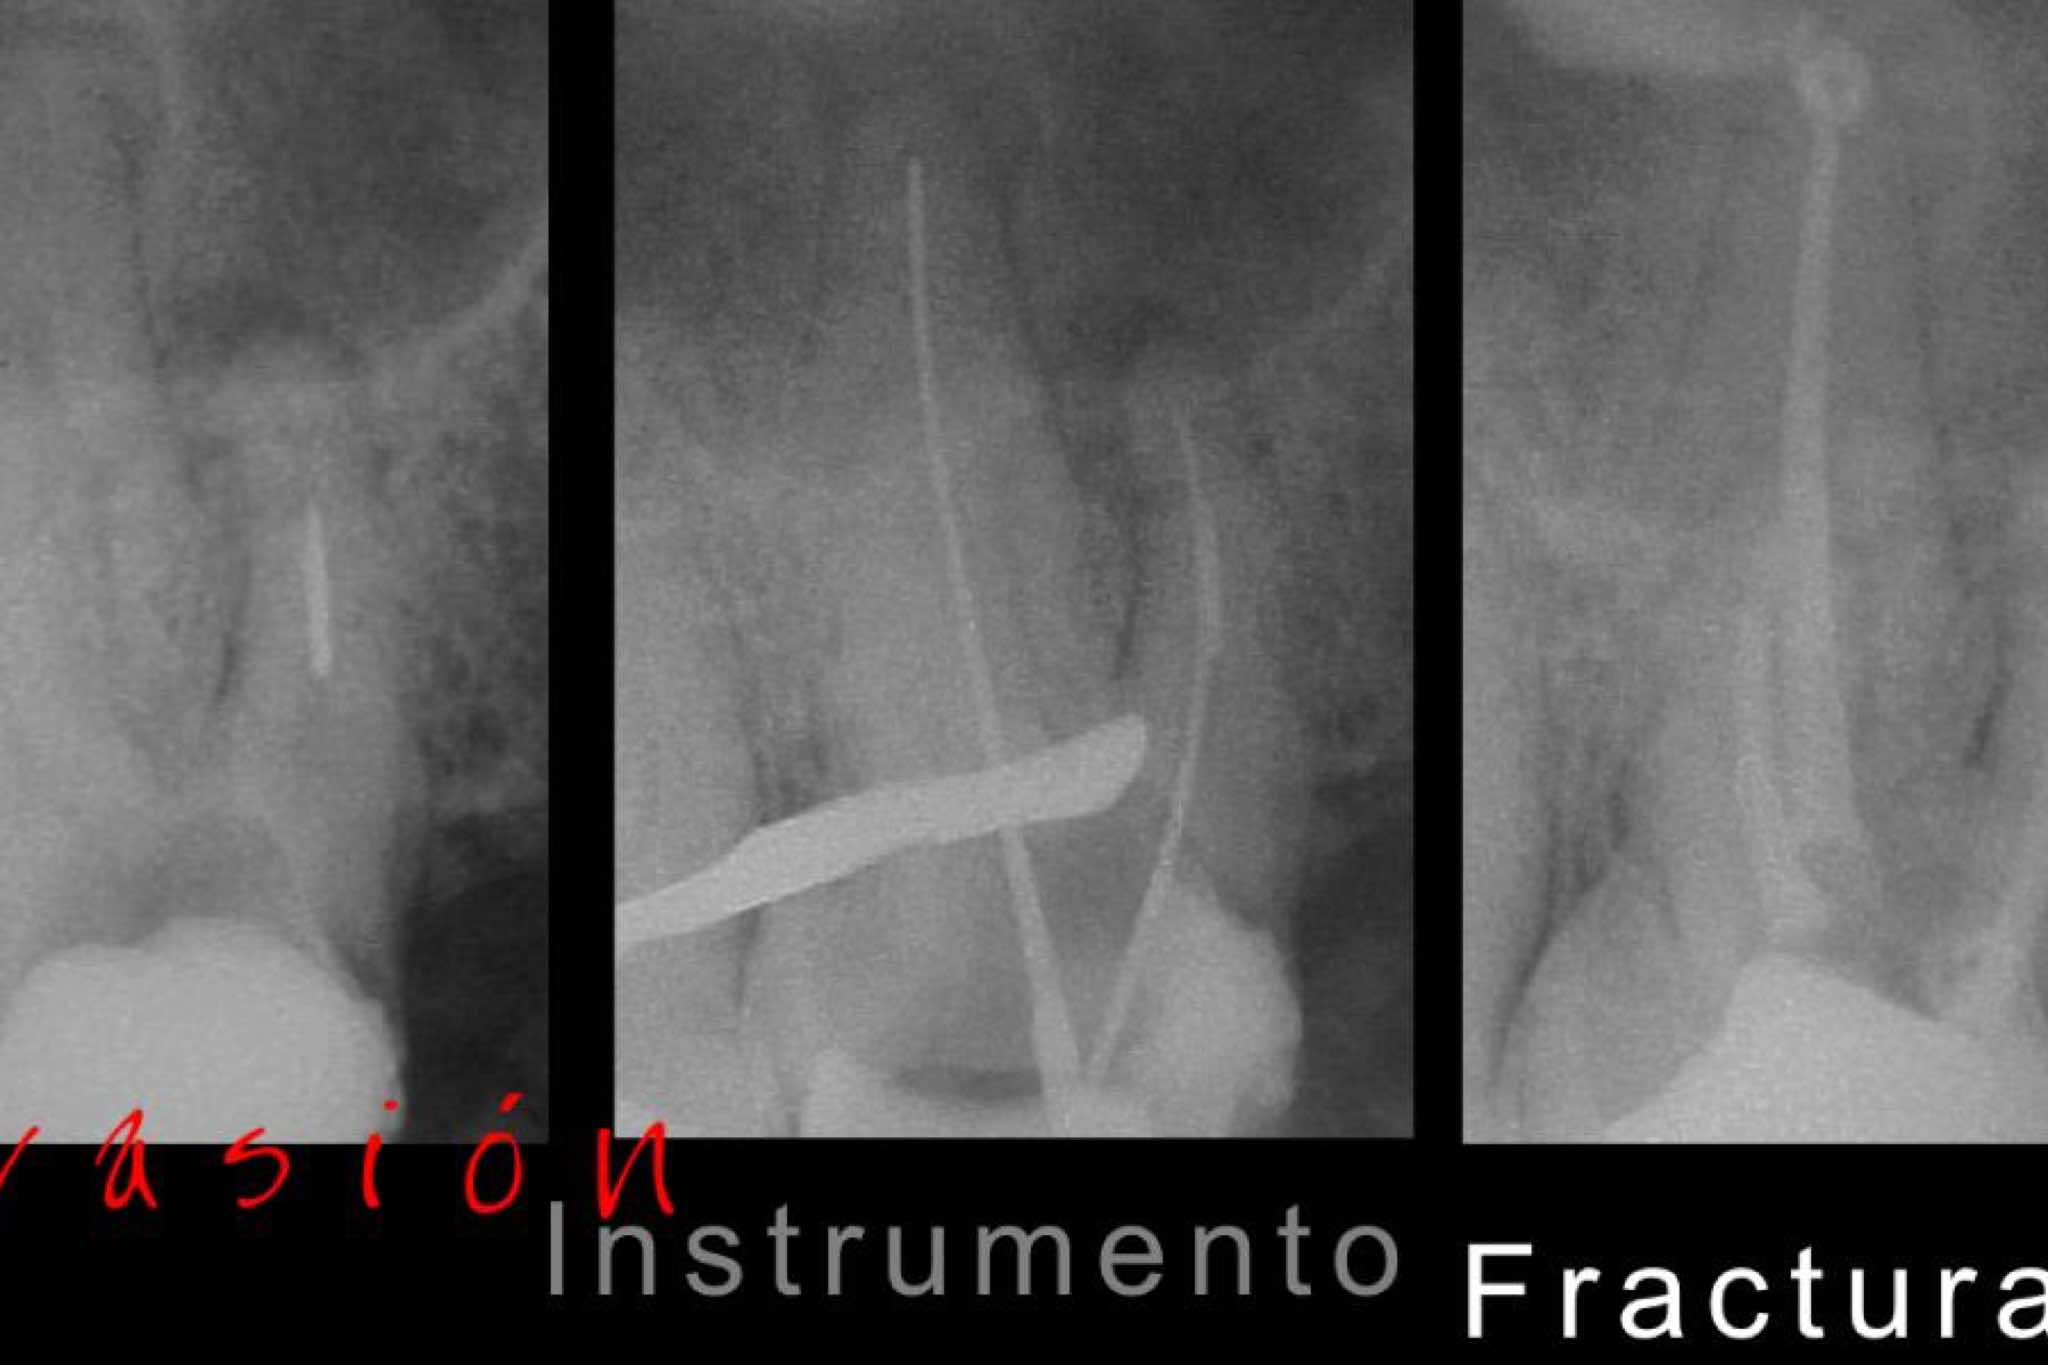

exibid_renocioninstrume2exibid_localizaciondeco2exibid_evasioninstrumen2exibid_retirodeposteyco2.jpegexibid_fracturavertical2exibid_retratamietoycir2